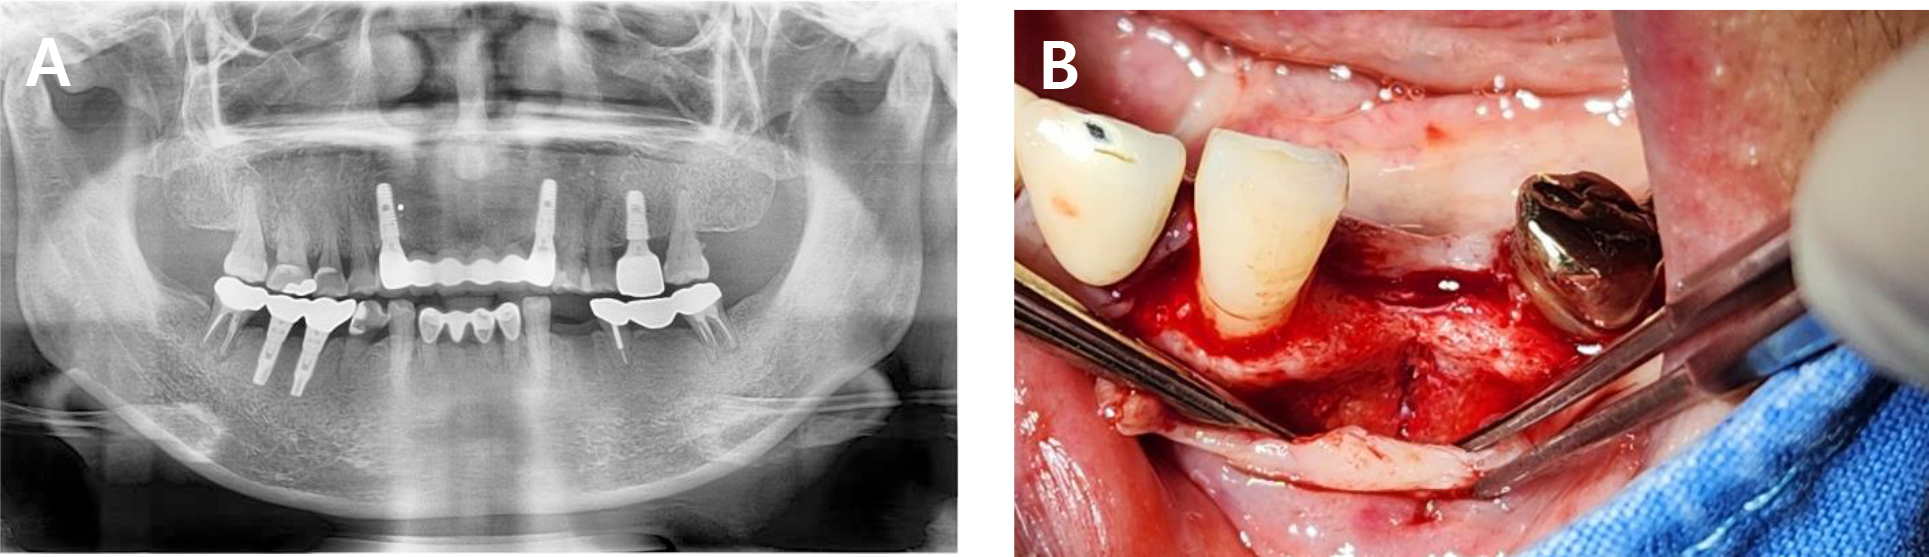

A 57-year-old female undergoing continuous ambulatory peritoneal dialysis at our hospital for end-stage renal disease visited our clinic for implant placement at the mandibular left first molar site, which had been lost due to chronic periodontitis. As alveolar bone loss progressed, the left mandibular second molar was considered non-restorable. As a result, the second molar was scheduled for extraction, and an implant was planned for the first molar site (Fig. 4).

Preoperative cone-beam computed tomography (CBCT) revealed horizontal alveolar bone deficiency due to long-term edentulism. To ensure long-term implant success, approximately 1–2 mm of HRA was considered necessary. Accordingly, simultaneous placement of a 4 mm diameter implant was planned, along with HRA using ADM loaded with rhBMP-2.

During surgery, the dehydrated ADM was carefully cut and folded to achieve a total thickness of approximately 0.6–1.2 mm. It was then immersed in 0.25 mg of rhBMP-2 dissolved in 0.5 mL of normal saline for 1 min. The prepared ADM was applied to the buccal bone defect and a titanium fixation screw was used to stabilize the graft material in position (Fig. 5). The surgical site was then carefully closed using simple interrupted sutures.